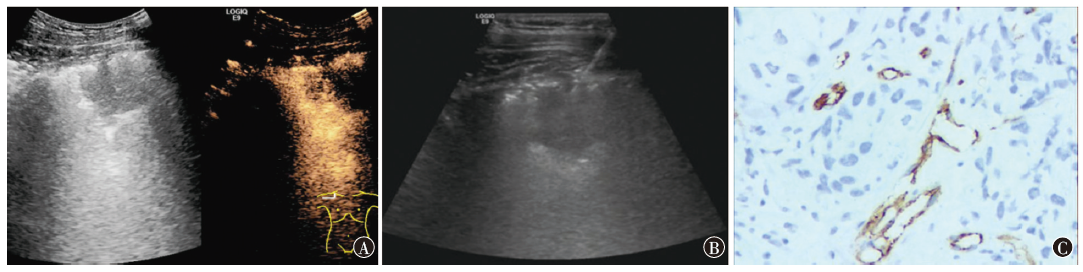

目的 比较超声造影(CEUS)和CT引导下经皮穿刺活检在周围型肺肿块诊断中的临床价值。方法 回顾分析2019年10月至2021年12月在南通大学附属肿瘤医院接受穿刺活检的90例周围型肺肿块患者的临床资料。按照穿刺引导方式的不同,分为CEUS引导的经皮穿刺活检组(CEUS组,40例)和CT引导的经皮穿刺活检组(CT组,50例),并评价两组在穿刺成功率、并发症发生率等方面的差异。同时,检测微血管密度(MVD)与CEUS参数之间的相关性。结果 CEUS组穿刺成功率高于CT组,但两组间差异不具有统计学意义[97.5%(39/40) vs. 92.0%(46/50),P=0.337];CEUS组并发症发生率明显低于CT组[0(0/40) vs. 12.0%(6/50),P=0.032]。而且与CT组相比,CEUS组穿刺次数少[(2.0±1.6)次 vs. (2.8±1.2)次,t=-2.43,P=0.018],穿刺时长短[(7.6±2.5) min vs. (15.3±2.6) min,t=-8.86,P<0.001],手术费用低[(1 308.4±545.6)元 vs. (2 046.4±645.3) 元,t=-2.01,P=0.046]。肺腺癌的MVD、CEUS峰值强度和增强指数均高于鳞状细胞癌[(25.4±4.9)个/HP vs. (16.6±7.3)个/HP,t=3.43,P=0.002;(46.9±6.5) db vs. (36.8±5.4)db,t=4.12,P<0.001;5.2±1.4 vs. 4.1±1.2,t=3.27,P=0.006]。肺鳞状细胞癌和肺腺癌的CEUS峰值强度、增强指数均与各自病灶内MVD呈正相关(鳞状细胞癌:r=0.66,P<0.001;r=0.56,P<0.001;腺癌:r=0.62,P<0.001;r=0.70,P<0.001)。结论 与CT相比,CEUS引导的经皮穿刺活检在周围型肺肿块诊断中并没有获得更高的成功率,但降低了并发症发生率,同时具有用时少、费用低、无辐射、可实时动态引导等优点,值得在临床中加强推广。另外,肺腺癌、鳞状细胞癌CEUS定量参数与MVD之间存在相关性,可能作为诊断依据。